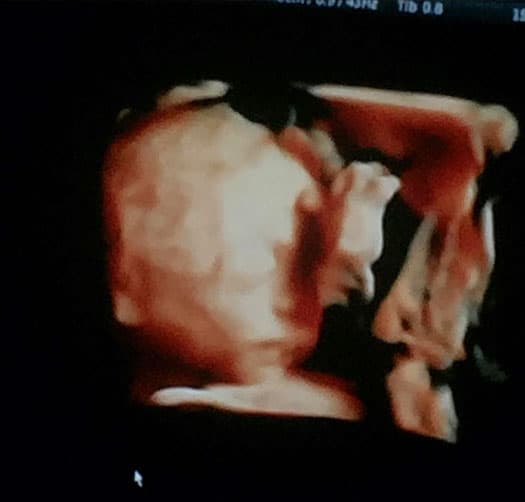

"Les presento a mi amor bebé!!! MARCELO!!! Duerme como su papá @pipooff con la mano en la cara y vean su pierna hará Yoga como yo!!", escribió la actriz cuando dio a conocer su ultrasonido.